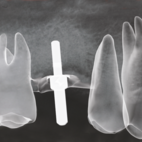

Seit Beginn der 80er Jahre setzen sich mehr und mehr Zahnimplantate als Alternative zu herkömmlichen zahnprothetischen Versorgungen in der Zahnmedizin durch – und das mit großem Erfolg. So belegen Studien, dass inzwischen 88 – 90% aller Implantate länger als 10 Jahre funktionsstabil sind. Dentalimplantate ersetzen die Wurzel eines fehlenden Zahns, d. h. sie werden im Rahmen eines chirurgischen Eingriffs in den Kieferknochen eingebracht. Nachdem der Knochen das Implantat – bestehend aus hochreinem bioverträglichen Titan – integriert hat, kann man an ihm den oder die fehlenden Zähne ersetzen.

© BioHorizons Implantate bieten eine Vielzahl von Versorgungsvarianten, die Ihnen als Patient ein großes Maß an Komfort und Lebensqualität ermöglichen, wobei die für Sie "richtige" Variante individuell abgestimmt werden muss. So kann man zum Beispiel einen fehlenden Einzelzahn, den man klassischerweise durch eine Brücke ersetzt hätte, durch ein Implantat mit einer Einzelzahnkrone wieder ersetzen,

© BioHorizons

ohne dabei die evtl. gesunden Nachbarzähne beschleifen zu müssen. Eine weitere Indikation besteht darin, Ihnen wieder festen implantatgetragen Zahnersatz zu ermöglichen, wo ansonsten nur eine herausnehmbare Total- oder Teilprothese möglich gewesen wäre. Falls Sie mit dem Halt Ihrer bisherigen Prothese unzufrieden gewesen sein sollten, besteht die Möglichkeit, durch gezielten Einsatz von Implantaten den Halt und die Passung der Prothese für Sie spürbar zu verbessern.